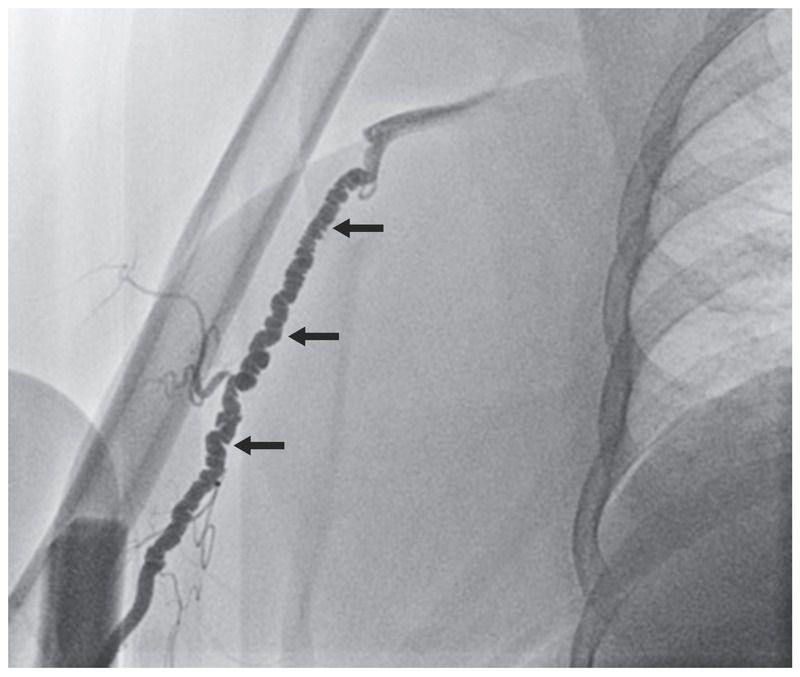

A 68-year-old woman presented with exertional dyspnea and chest pain, symptoms that suggested unstable angina. She had undergone coronary-artery bypass grafting 5 years earlier. Vascular examination revealed palpable radial pulses on both sides of the body. The results of Allen’s test, conducted with the use of plethysmography, were normal. Transradial coronary angiography was attempted, but there was difficulty advancing the guidewire and diagnostic catheter past the level of the elbow. Right brachial angiography revealed a “string of beads” pattern (arrows) that was consistent with fibromuscular dysplasia, a noninflammatory, nonatherosclerotic disorder of the blood vessels. Fibromuscular dysplasia is most commonly seen in the carotid and renal arteries but has been observed in nearly every arterial bed. Although many patients are asymptomatic, some have symptoms related to the affected arterial bed, such as hypertension, renal failure, stroke, abdominal pain, or claudication of the legs. Coronary angiography was completed by means of the right femoral artery, which revealed no indication of fibromuscular dysplasia but did reveal stable coronary artery disease with patent bypass grafts. The patient’s chest pain resolved and was attributed to a noncardiac cause. She was discharged the next day, and there were no further sequelae.